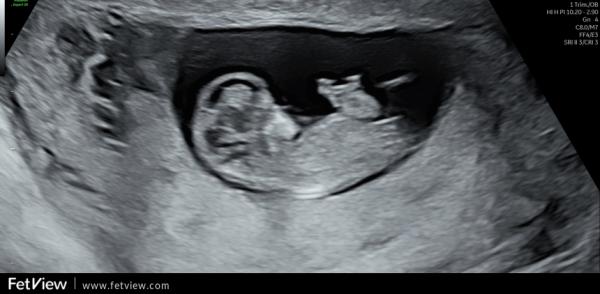

Huhu liebe Letti, ich gucke auch immer mal gerne in die anderen Gruppen rein 🤭 Deine Bilder muss ich wirklich sagen sind sehr schwierig. Würde aber einen Hauch mehr zum Jungen tendieren. Beim Mittleren ist über dem sticht noch ein kleiner kurzer Strich, den haben die Mädels nicht. Ebenso fehlt diese typische Mädchen gabelung vorne. Und bin mir nicht ganz sicher, ob der obere Strich bei (ich glaube bei dem letzten Bild war es) ein ganz kleines mini bisschen mehr nach oben geht. Ich kann es mir aber auch einbilden. Ich muss ehrlich sagen, dass ich die Nub Theorie unfassbar spannend ist und am liebsten den ganzen Tag so Bilder angucken könnte und neugierig bin, was es letztendlich dann ist 🤭

Oh, ich bin ja ganz bei dir. Finde das auch total spannend. Auch wenn das natürlich keine 100% Garantie gibt. Ich muss gestehen, dass ich mich danach ein wenig reingelesen habe und das Ganze trotzdem nicht 100% verstanden habe 🤔😃 Meine Bilder sind aber auch nicht so eindeutig, wie die, die man im Internet (meist) findet. Gerade beim letzten Bild hätte ich eher auf ein Mädchen getippt, weil das für mich so parallel aussah, wo ich eingekreist habe 🥰 Der weiße "Strich/Fleck" oberhalb von dem orangenen Kreis gehört zum Bein. 🤭 Einfach spannend 😍

Ich find es halt interessant, weil die Ärztin bei der Feindiagnostik auch damit anfing und das nochmal erklärt hatte. Schade, dass man den Nub nicht so genau erkennen kann. Oder man kann ihn sehen aber unser ungeschultes Auge bekommt es nicht gebacken 😂 Ich weiß was du meinst. Hab dein Bild frecher weise einfach mal "bemalt" um zu zeigen, was ich meine.

Genau. Das letzte Bild war es. Der untere Strich geht nach unten, der obere nach oben. Es sind nicht beide Parallel verlaufend nach unten.